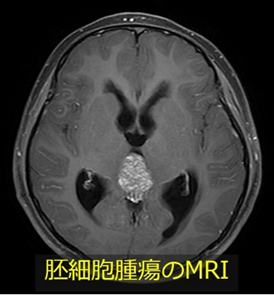

生殖系に発生するものと類似の腫瘍が脳内にも発生することが知られています。比較的良性の性格を持つ胚腫や奇形腫、悪性度の高い絨毛癌や卵黄嚢腫瘍など様々なタイプに分類されており、これらをまとめて胚細胞腫瘍といいます。

治療方法は各タイプによって異なりますが、基本は手術と放射線治療・化学療法です。どのタイプか調べるため多くの場合まず生検術が必要になります。水頭症を合併することが多いため、当科では生検術と第Ⅲ脳室底開窓術を同時に行うことで迅速な診断と治療を行い、患者さんの負担を軽減するよう工夫しています。